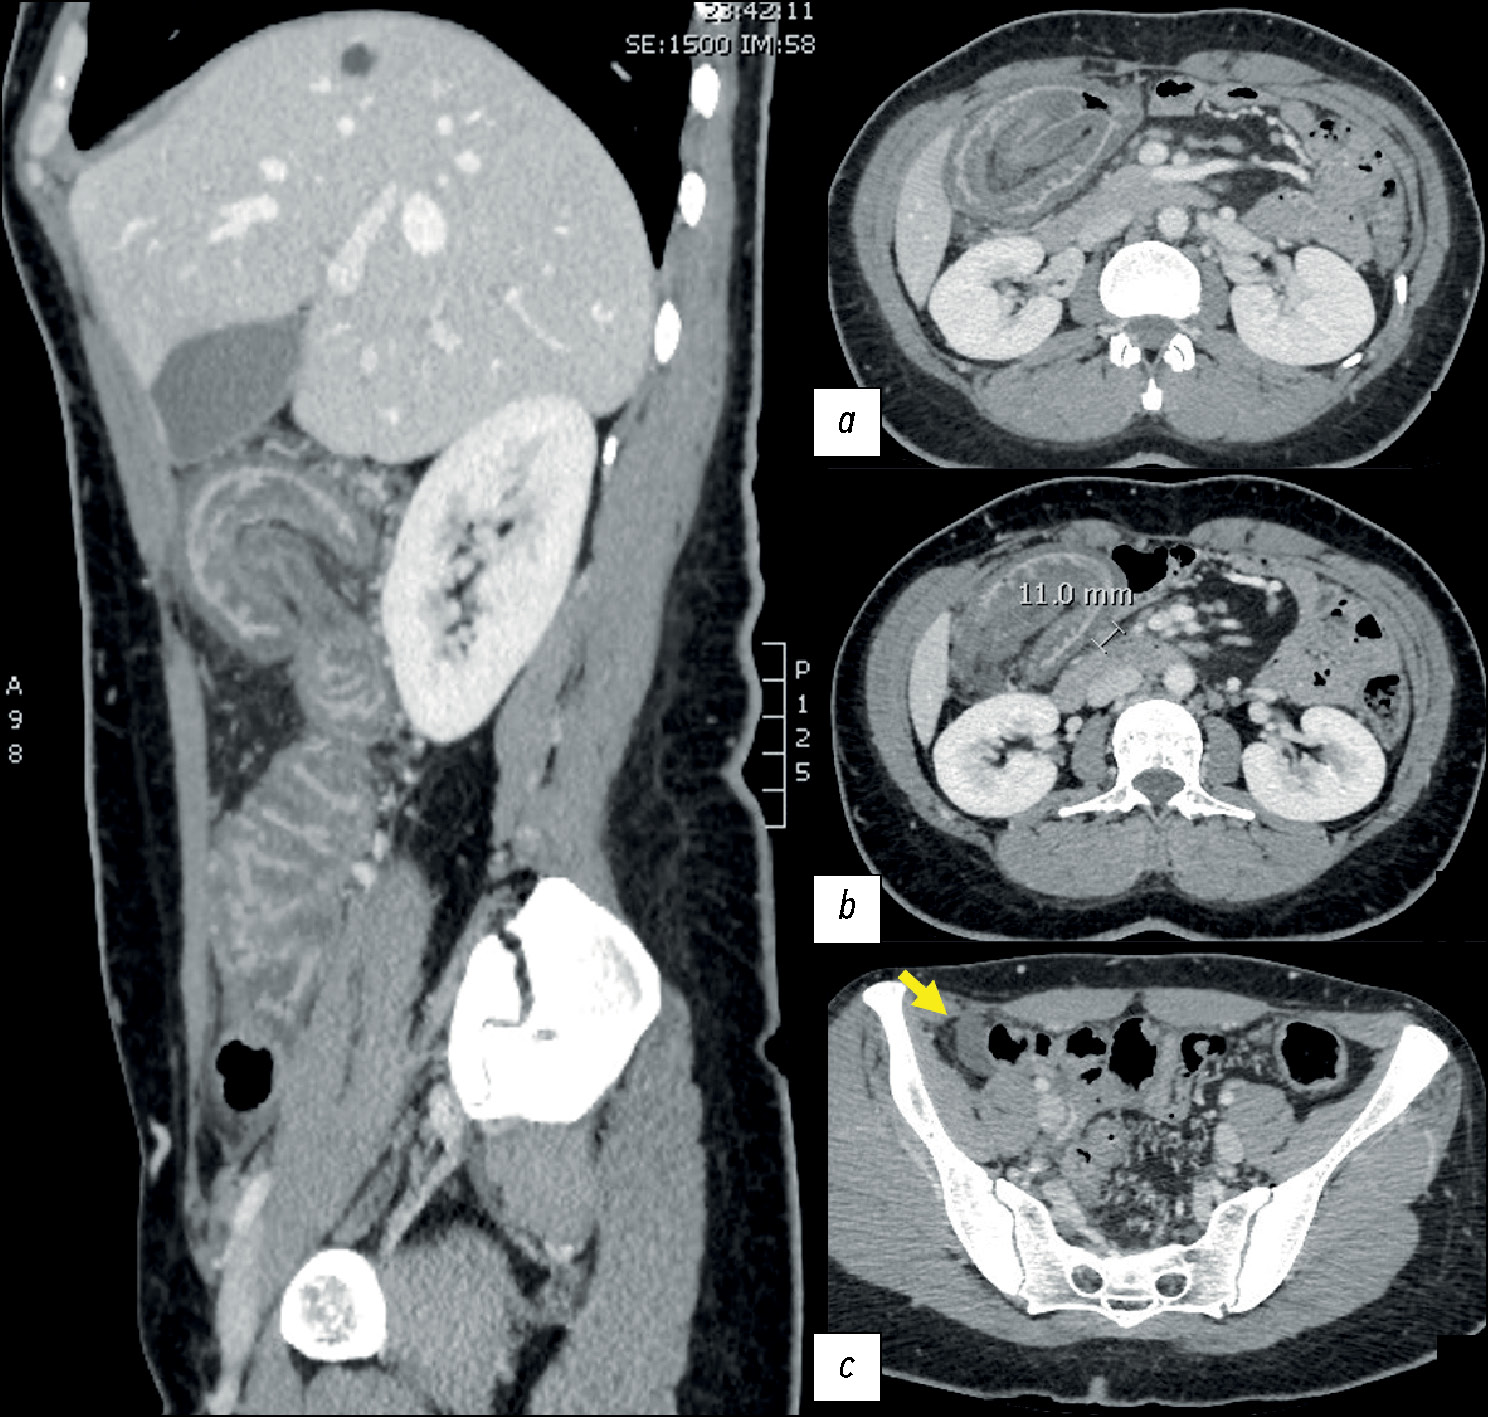

To exclude any possible causes of intestinal obstruction, computed tomography (CT) was performed before and after the administration of intravenous iodinated contrast medium. CT revealed an enterocolic invagination involving the ileocecal valve and the cecum with diffuse edematous thickening of the colonic parietal walls. Edematous strains in the adjacent peritoneal fat, satellite lymphadenopathy levels, and a small amount of fluid collection in the right iliac fossa were also present (Fig. 1).

Fig. 1. Abdominal computed tomography, portal phase. Sagittal multiplanar reconstruction: (a) enterocolic invagination with the involvement of the mesenteric fat and vascular structures. Thick edematous walls, stranding of the surrounding fatty tissue (b), and satellite nodes (11 mm in c).